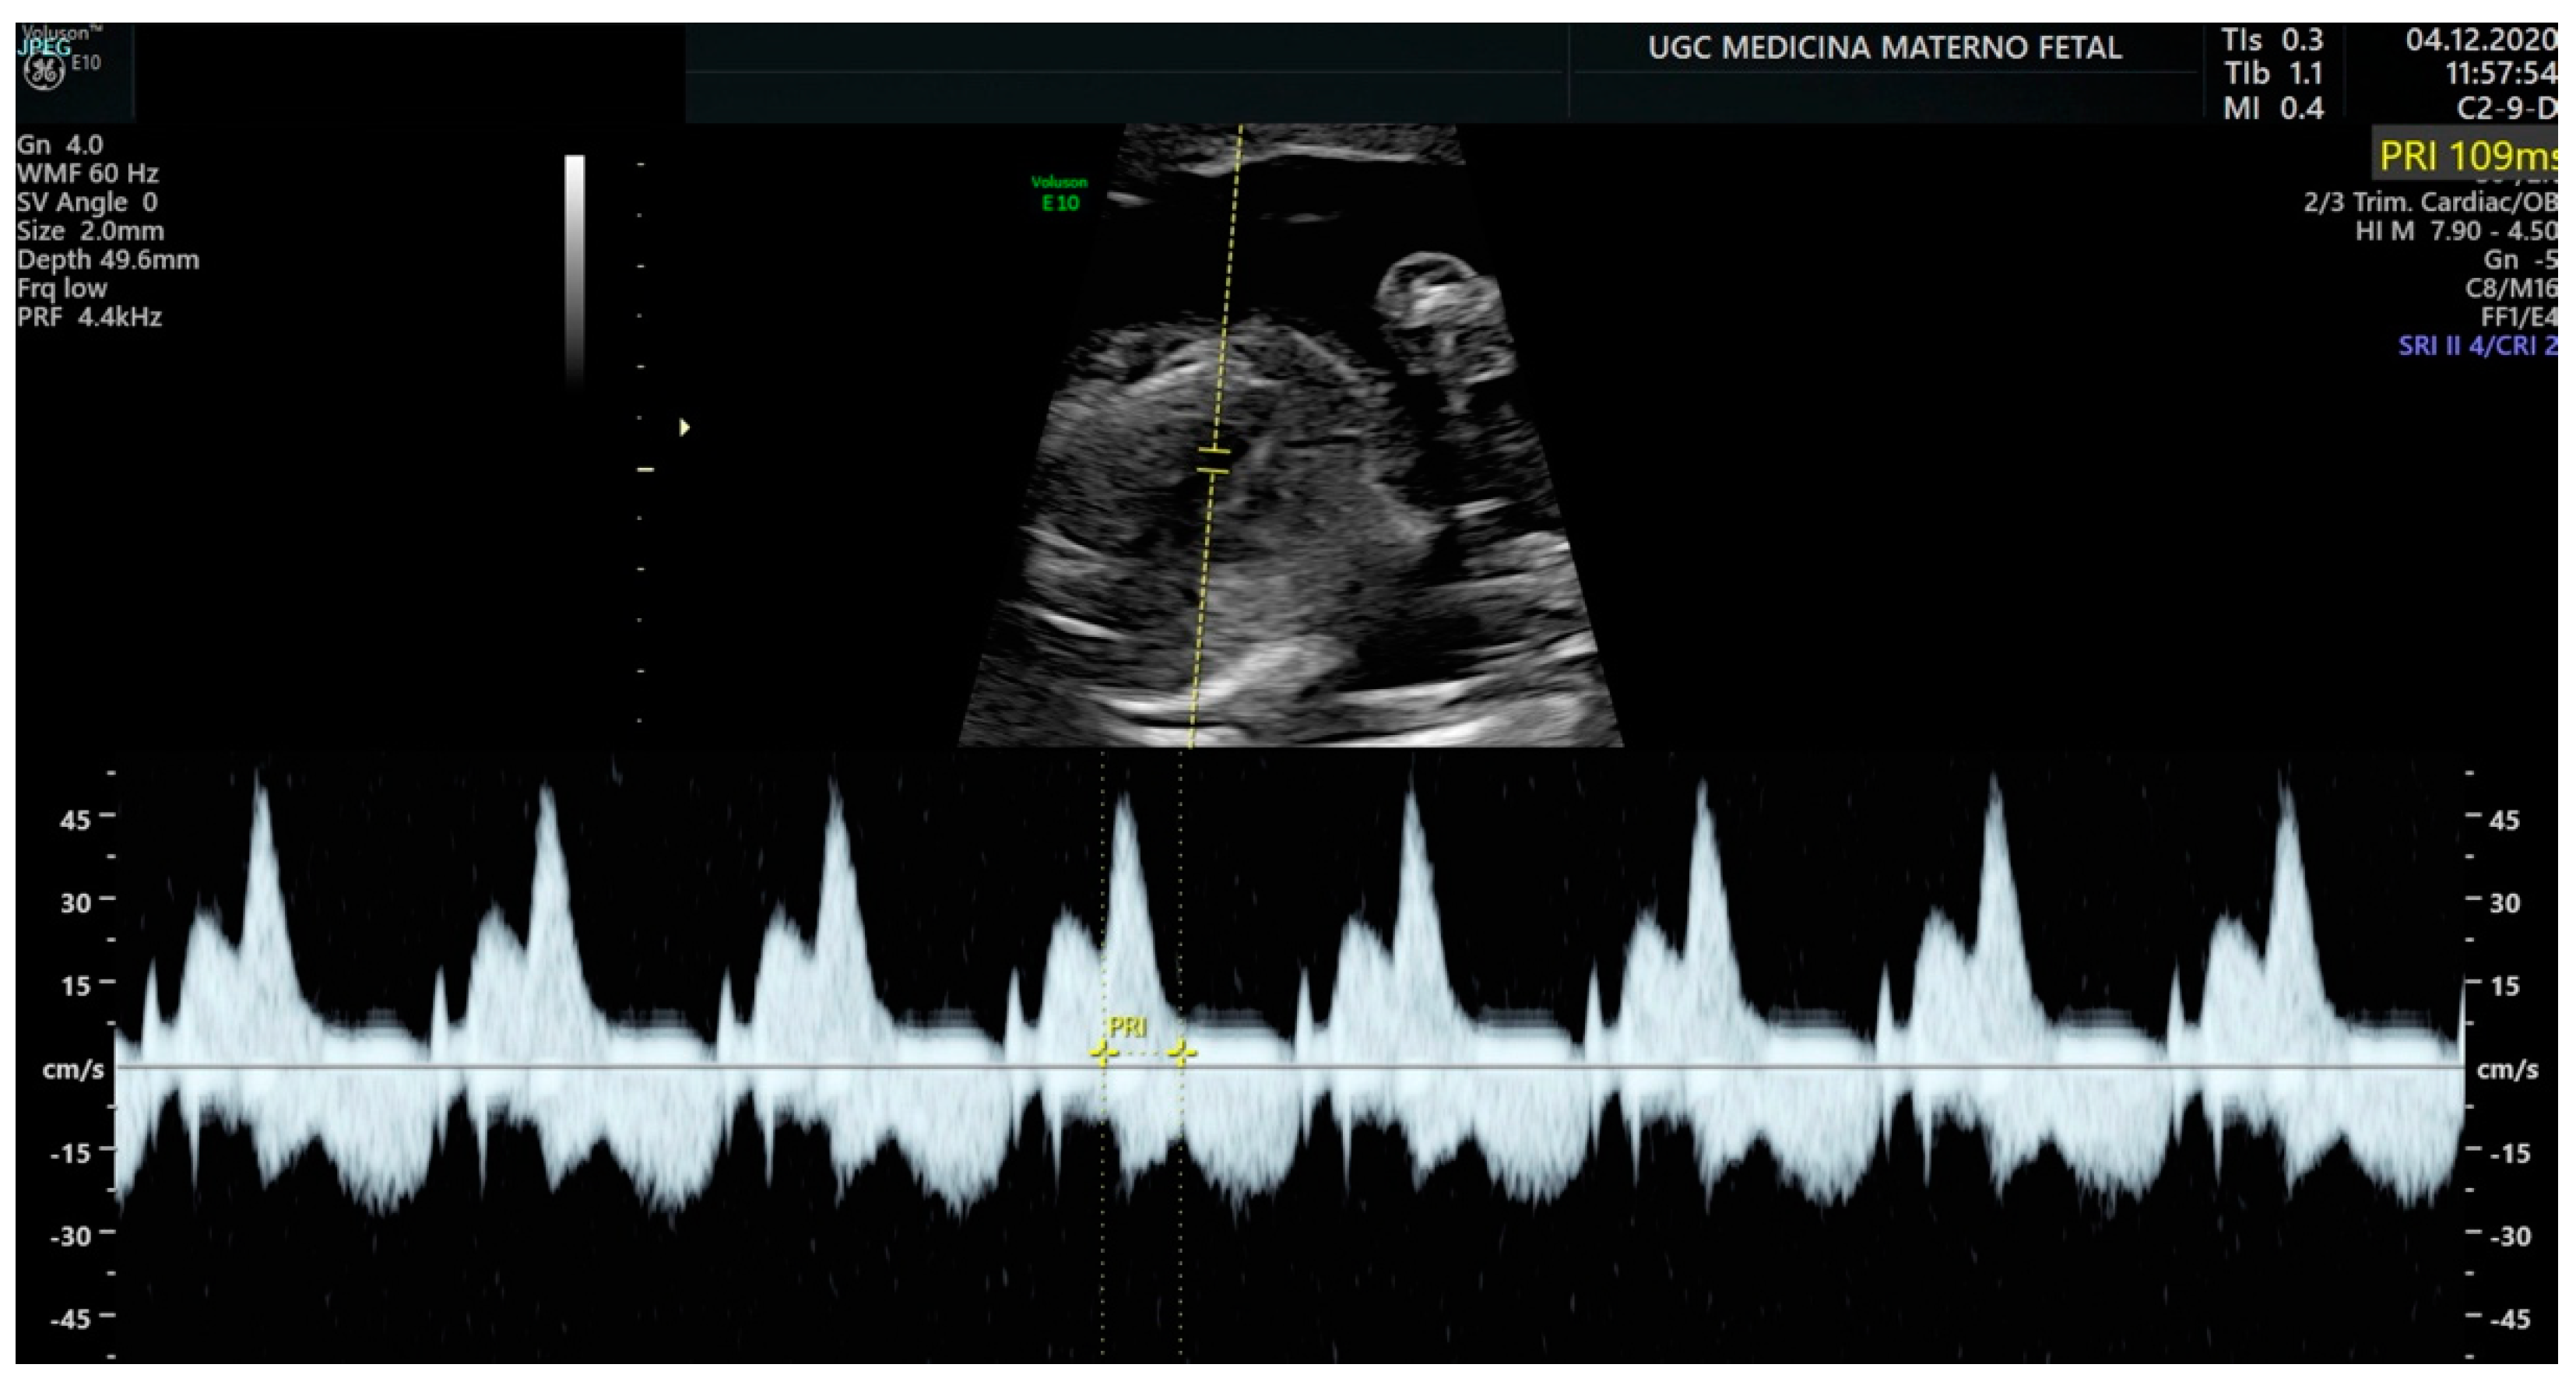

Pulsed-wave Doppler makes it possible to determine mechanical phenomena and evaluate atrial and ventricular contractility and their relationship. Although there are different windows for its acquisition, the left ventricular outflow tract is usually used. This allows us to capture the time it takes for the impulse to travel from the atrium to the ventricle (AV interval), which is the equivalent of the PR interval detected by the electrocardiogram (Figure 1).

Figure 1.

Measurement of the AV interval (PR) by pulsed Doppler in the fetal left ventricular outflow tract.

To classify tachyarrhythmias, the efficacy of AV and VA intervals based on Doppler echocardiography is inquired [20,21,22,23]. Short VA SVT is the typical pattern in reentry tachycardia, while long VA SVT suggests atrial ectopic tachycardia or permanent junctional reciprocating tachycardia. Regarding this, it is important to highlight that the size of the fetal atrium is an important factor in the propagation of atrial flutter, achieving its critical size at around 27–30 weeks of GA [24,25].